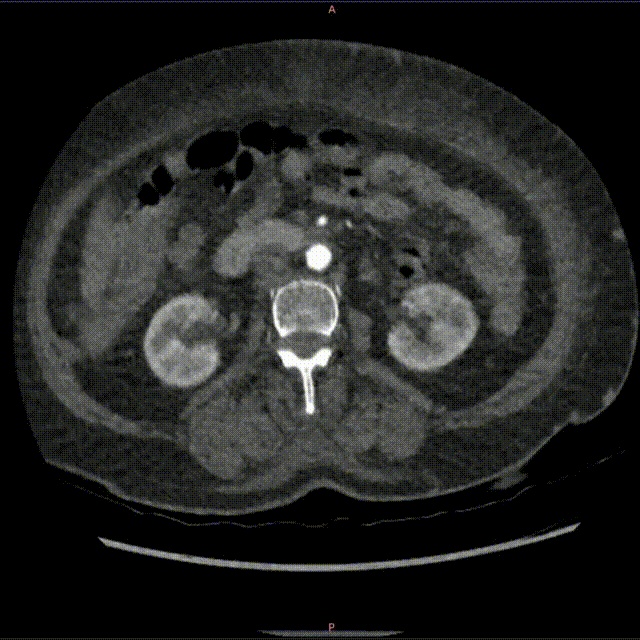

为了进一步探明真相、排除静脉外占位性病变,团队随即为患者安排了下肢CT血管造影(CTA)检查。检查结果一方面证实了患者左髂静脉受动脉压迫所致闭塞的事实;另一方面,一个关键性线索浮出了水面——影像上出现了左下肢静脉“早显”的现象,这通常强烈暗示动脉和静脉之间存在着异常沟通。

2 CTA可见左髂静脉受动脉压迫闭塞,同时左下肢静脉早显(1) 00_00_00-00_00_30.gif

血管造影影像显示患者左髂静脉受动脉压迫闭塞、左下肢静脉出现“早显”现象